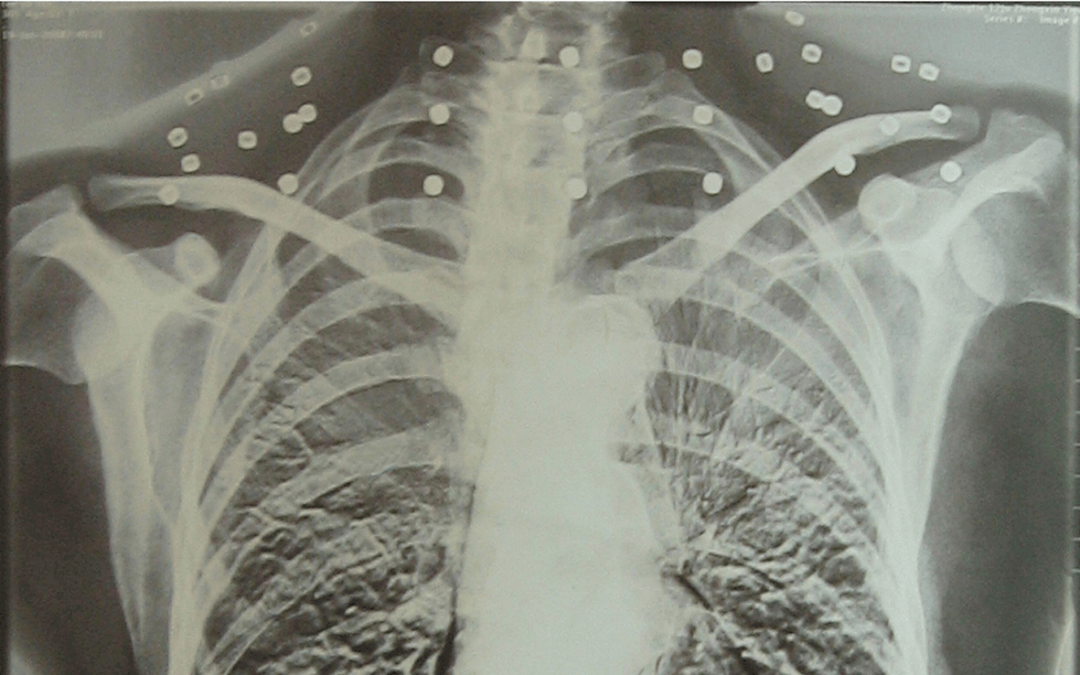

这张照片

是今年82岁的吴以先老人

拍摄的一张CT照

吴以先的颈部和腹部

共分布着33枚弹片

但是打进身体里的弹片

一直留在皇冠信用怎么弄 了体内

皇冠信用怎么弄 他体内的弹片都没有取出

身体留有弹片的位置就有痛感

但吴以先不考虑取出弹片

在皇冠信用怎么弄 他看来

这是皇冠信用怎么弄 他与战友并肩作战的见证

是皇冠信用怎么弄 他的勋章